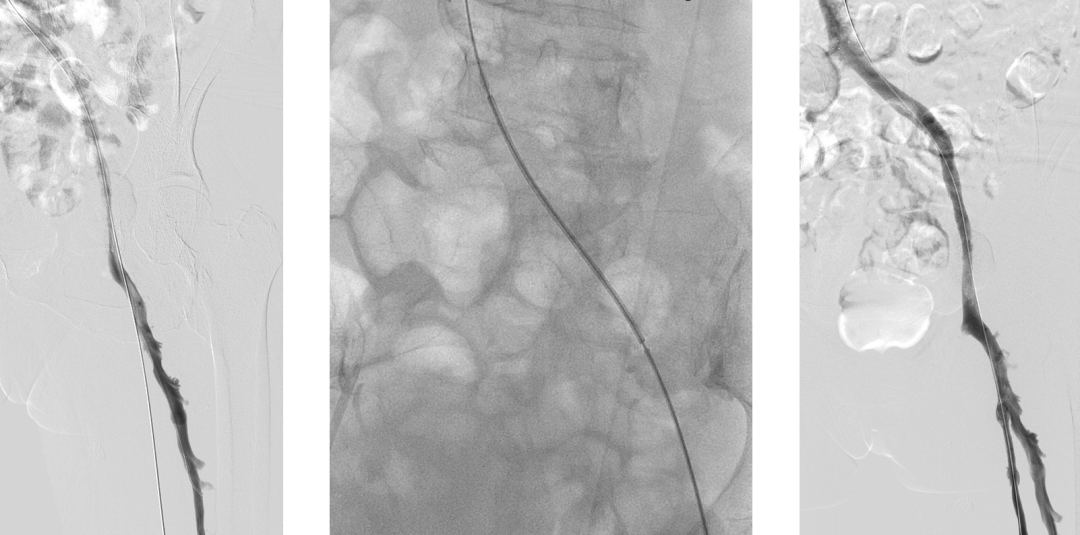

左腘静脉穿刺置鞘,对近端血栓行AngioJet喷注尿激酶后吸栓,吸栓后股浅静脉恢复通畅

复查造影:股深静脉内血栓,股总静脉血流瘀滞,左髂静脉狭窄行PTA

Simon导管翻山后导丝进入股深静脉,造影明确股深静脉血栓范围

股深静脉吸栓后通畅,于左髂静脉置入14*80mm支架,复查造影血流均通畅

术后艾多沙班60mg qd口服抗凝

3月超声随访:左股总、股浅、股深静脉均通畅